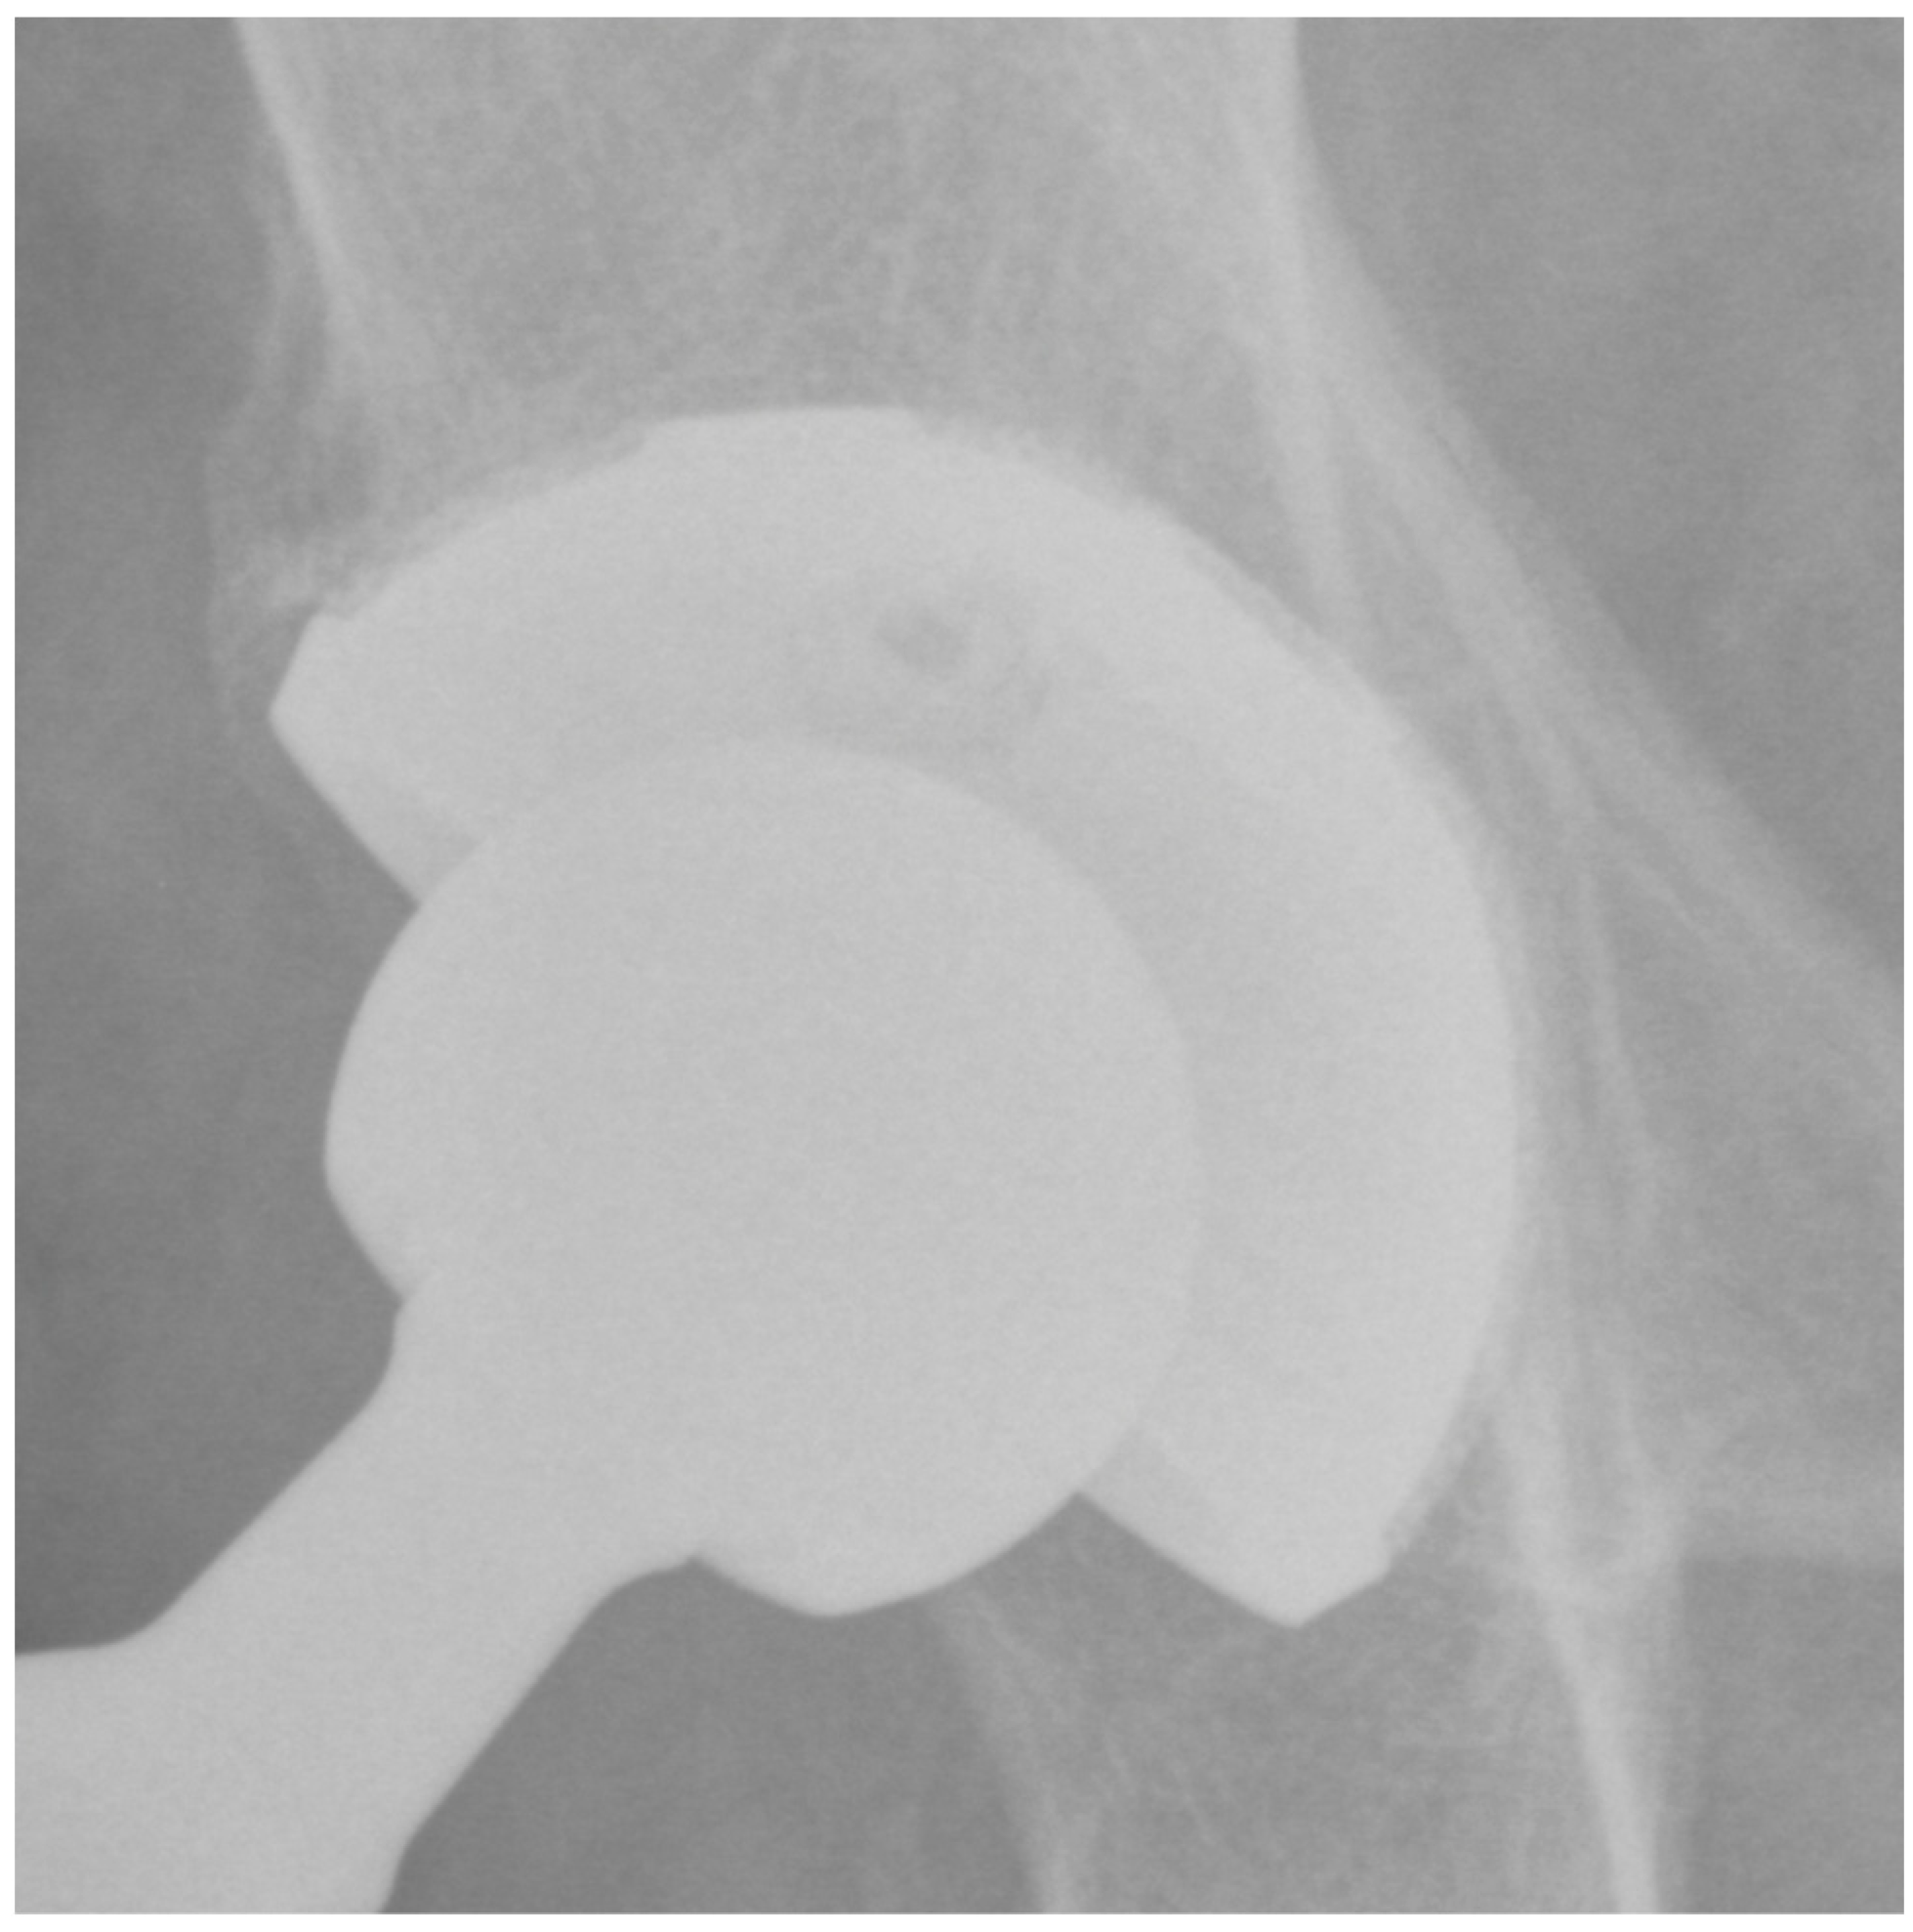

At the last follow-up, none of the patients showed signs of radiolucency. The presence of a superolateral buttress was detected in 95 (91.3%) patients. The presence of a medial stress shield was detected in 85 (81.7%) patients. The presence of radial trabeculae was detected in 70 (67.3%) patients, while the presence of an inferomedial buttress was detected in 75 (72.1%) patients. As a result, at least three signs (3 points) of osseointegration according to Moore et al. [22] were observed in all patients. In detail, 40 (38%) patients showed a very well osseointegrated cup (5 points) (Figure 2), 40 (38%) patients showed a well osseointegrated cup (4 points), and 24 (24%) patients showed an osseointegrated cup (3 points). There were three (2.8%) cases of bone sclerosis around the acetabular component. Heterotopic ossifications occurred in five (4.8%) patients; all cases were classified as grade 1.

Figure 2.

Plain pelvis radiograph of a 79-year-old male patient at 4-year follow-up with 5 points according to Moore.